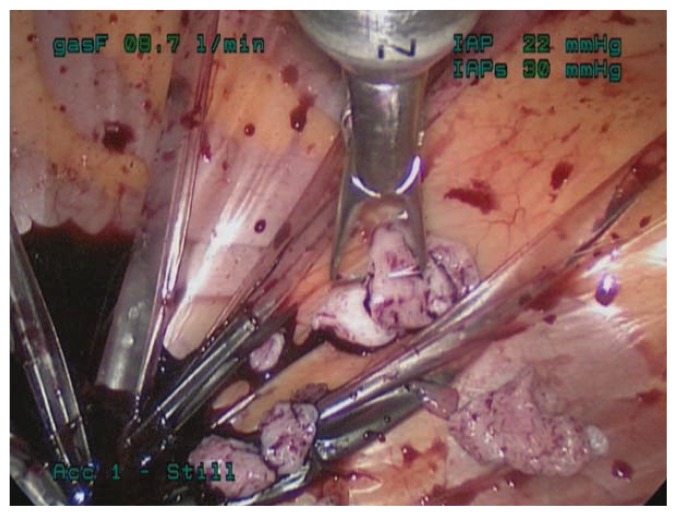

Even with a careful preoperative workup, some malignancies will be missed. Therefore, to limit both benign and malignant uterine tissue dissemination, morcellation can be contained within a bag. Several such techniques have been described. For example, specimens can be placed in a bag and morcellated by hand either through the vagina or through a minilaparotomy incision (see Figure 2). Alternatively, power morcellation can be performed inside a bag (see Figure 3).5 In 2014 Cohen et al. described the safety and feasibility of power morcellation within a large insufflated containment bag, and then in a follow-up study demonstrated negative cytologic washings after morcellation in vitro.50, 51 In 2015, Winner et al. found that morcellation within an insufflated bag took twenty minutes longer than uncontained morcellation, with no increase in complications.52 And in 2016, Cohen et al. published a prospective in vivo study in which uterine tissue was stained with dye before morcellation, and the pelvis was inspected after morcellation.53 Dye/tissue leakage was noted in 7 out of 76 cases, although the authors noted that most of the dye leakage was likely due to the method of introduction; actually spillage of tissue fragments was only noted in one case. Together, these studies indicate that power morcellation within a containment bag is feasible and effective, although efforts should be made to improve the technique. In 2016, the FDA approved the first bag for contained morcellation.54

Figure 3.

Power morcellation contained within an insufflated bag.